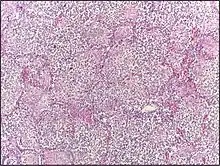

![]() | Dysgerminoma | Dysgerminoma characterized by uniform cells resembling primordial germ cells separated by fibrous septa with lymphocytes. | Category: Histopathology of ovarian dysgerminoma | Ovarian dysgerminoma |